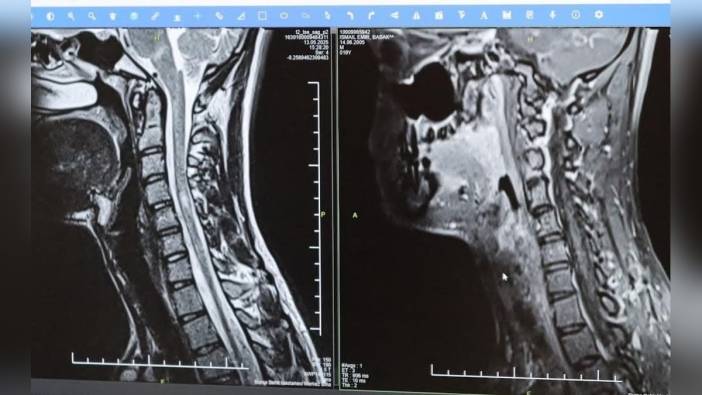

MS'in ataklar şeklinde seyredebildiğini ve en sık görülen formun bu olduğunu belirten Prof. Dr. Kamışlı, birdenbire ortaya çıkan bir şikayetin zamanla azalabileceğini veya kaybolabileceğini söyledi. Hastalığın bir diğer formunun ise progresif yani ilerleyici form olduğunu ve bu formda hastalığın yavaş yavaş ilerlediğini açıklayan Kamışlı, MS'in her hastada farklı seyrettiğini ve bu nedenle tek tip bir MS hastalığından bahsetmenin mümkün olmadığını ifade etti. Prof. Dr. Kamışlı ayrıca, hastalığın tanısının ne kadar erken konulup tedaviye ne kadar erken başlanırsa hastaların günlük hayatta aktif ve üretken bir şekilde devam etmelerinin o kadar kolaylaşacağını, günümüzde MS ile ilgili çok fazla gelişme olduğunu ve tedavi seçeneklerinin arttığını sözlerine ekledi.